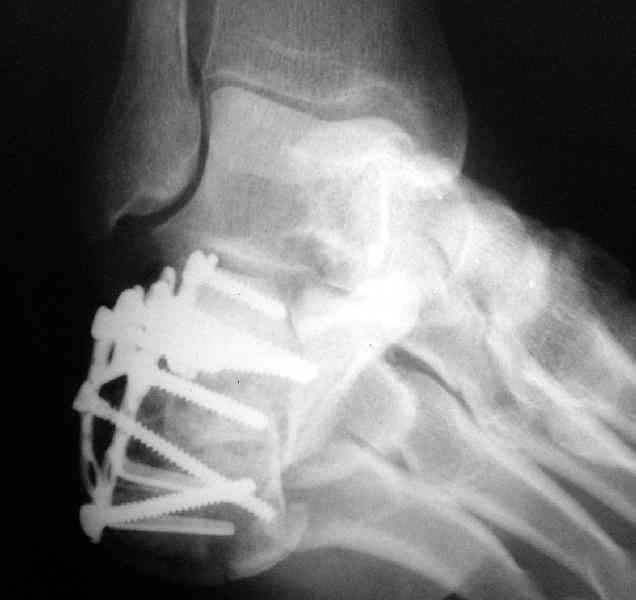

Какой предпочитаете доступ? Нет ли показательных рентгенснимков?

Открытый и закрытый способы лечения.